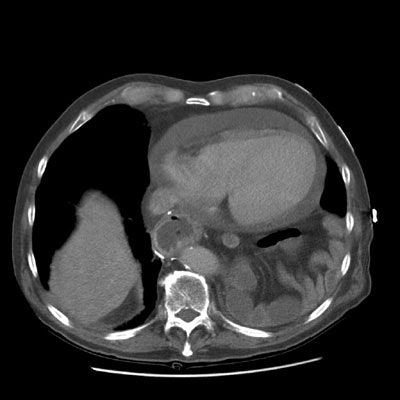

Pericardial effusion:

The exam below demonstrates a low density pericardial fluid collection. The effusion can be seen to extend into the pericardial recesses anterior to the ascedning aorta and the area posterior to the pulmonary outflow tract (anterior to the left upper lobe pulmonary vein). The patient has had a prior gastric pull-through procedure.